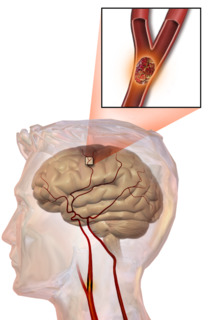

Illustration of an embolic stroke, showing a blockage lodged in a blood vessel.

In thrombotic stroke, a thrombus[39] (blood clot) usually forms around atherosclerotic plaques. Since blockage of the artery is gradual, onset of symptomatic thrombotic strokes is slower than that of a hemorrhagic stroke. A thrombus itself (even if it does not completely block the blood vessel) can lead to an embolic stroke (see below) if the thrombus breaks off and travels in the bloodstream, at which point it is called an embolus. Two types of thrombosis can cause stroke:

Embolic stroke

An embolic stroke refers to an arterial embolism (a blockage of an artery) by an embolus, a traveling particle or debris in the arterial bloodstream originating from elsewhere. An embolus is most frequently a thrombus, but it can also be a number of other substances including fat (e.g., from bone marrow in a broken bone), air, cancer cells or clumps of bacteria (usually from infectious endocarditis).[45]

Because an embolus arises from elsewhere, local therapy solves the problem only temporarily. Thus, the source of the embolus must be identified. Because the embolic blockage is sudden in onset, symptoms usually are maximal at the start. Also, symptoms may be transient as the embolus is partially resorbed and moves to a different location or dissipates altogether.